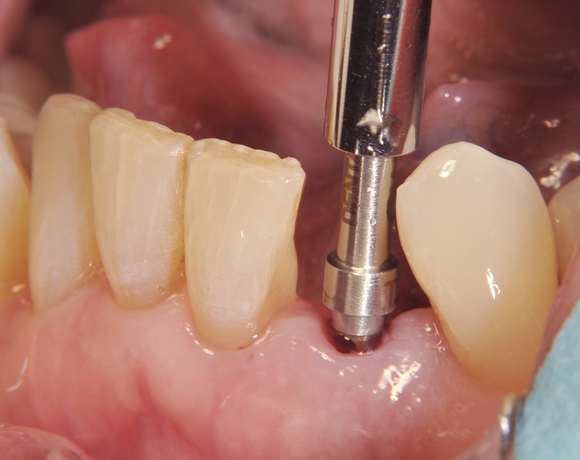

Am Beispiel dieses Patientenfalls wird gezeigt wie ein Einzelimplantat für den Unterkieferfrontzahn 33 eingesetzt wird.